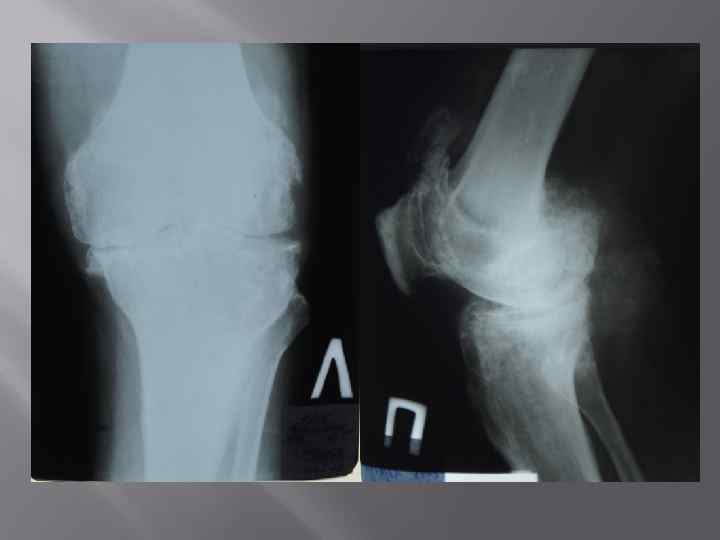

Жалобы На боли в области коленных суставов, их припухлость, боли в плечевых суставах, ограничение подвижности в них, боли в области локтевых суставов, ограничение сжатия пальцев кистей в кулак, множественные узловые образования в области суставов кистей, скованность и боли в пояснице.

Объективно: • У пациента наблюдается дефигурация 1 плюснефаланговоговых суставов. Дефигурация левого коленного и левого локтевого суставов. Объем пассивных и активных движений в коленном суставе снижен , сгибание составляет 60 градусов, разгибание до угла 10 градусов. Объем движений в голеностопных суставах снижен и составляет 0/10 гр. Определяются тофусы в области пястно-фаланговых суставов обеих кистей, локтевых суставов, болезненность при пальпации, ограничение в объеме движений в шейном, грудном и поясничном отделах позвоночника, грудной кифоз, сглаженный поясничный лордоз, положительные симптомы сакроилеита с обеих сторон.

КЛИНИЧЕСКИЙ ДИАГНОЗ: Подагра хронического течения: рецидивирующий подагрический полиартрит (тофусы), в сочетание с анкилозирующим спондилоартритом аксиальной формы высокой степени активности, поздняя стадия, рентгенологическая стадия 4. ФК III. ХБП, 3 стадии, хронический тубоинтерстициальный нефрит с исходом в нефросклероз ( подагрическая нефропатия ), кисты почек (р СКФ CKD EPI 35 мл/мин/1. 73 м 2). Гипертоническая болезнь 2 стадия, риск 3.